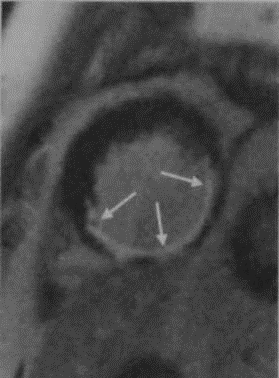

3. МРТ при отосклерозе:

• Т2 ВИ:

о Тонкосрезовая МРТ Т2 высокого разрешения: отосклероз (даже распространенный) может не определяться

о В больших бляшках может обнаруживаться легкое повышение интенсивности сигнала

• Т1 ВИ С+:

о Контрастирующиеся точечные очаги в медиальной стенке среднего уха (ФОто) ± перикохлеарные очаги в костном лабиринте (КОто):

- Наиболее очевидны при сочетании ФОто и КОто

о В тяжелых случаях контрастирующиеся участки могут обнаруживаться повсюду в костном лабиринте

о МРТ Т1 С+: контрастирующиеся очаги в активной фазе отосклероза

о При МРТ высокого разрешения (Т2) можно пропустить отосклероз

(Справа) При аксиальной МРТ Т1ВИ С+ FS у этого же пациента определяется контрастное усиление спереди от овального окна (щель перед окном) и вокруг улитки (фенестральный и кохлеарный отосклероз, соответственно).